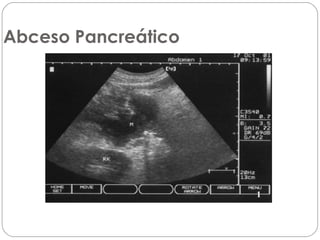

Abceso Pancreático

Absceso

Es una colección bien circunscrita de pus con mínima o

ninguna necrosis. Puede ocurrir en ataques inicialmente

graves asi como en los que inician como leves. También

se usa la bacteriología percutánea como único medio de

diagnóstico